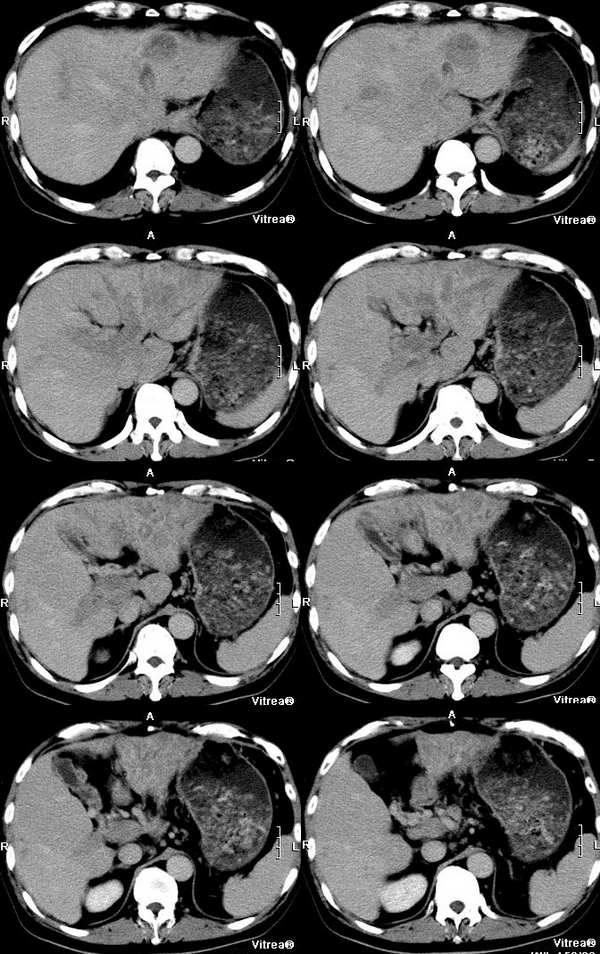

男性,58岁,肝硬化数年,近几个月出现黄疸,腹胀,食欲下降,尤其双下肢浮肿明显。超声提示肝脏多个结节。ct三期扫描图像如下:

动脉期:

门脉期:

平衡期:

动静脉期见门静脉,下腔静脉增宽,无强化,右心房有无强化的低密度影,肝左叶轻度不均匀强化,平衡期见病灶密度减低,肝内胆管扩张.肝尾叶增大.动脉期见肝左静脉明显强化并向右心房的特异性侧支循环.

肝左叶不规则肿块,血供不丰富,早期强化不明显,三期符合肝癌块尽快出的特点。门静脉、腔静脉近右房段增粗,早期见癌栓滋养血管强化明显。

肝静脉:在动脉期的第一张图片上就可以看到右心房的充盈缺损和下腔静脉近心段的明显增粗,增粗的下腔静脉内部可以见到点状、条状的强化血管影,这些强化的血管影是什么来源?这些高密度影蜿蜒曲折,和主动脉同时显影,所以只能考虑为主动脉的分支血管之一。到门脉期和平衡期,右心房的充盈缺损更加明显了,肝静脉和下腔静脉的强化非常微弱,肝段下腔静脉的管腔十分狭窄,但肝外段的下腔静脉明显的饱满,这是由于右心房的充盈缺损和下腔静脉近心段的栓子梗阻造成的。在动脉期肝左叶有一条横行血管也非常引人注目,考虑为肝左静脉的可能,但其汇入腔静脉端呈一盲端,估计终止于栓子部位,该血管的过早显影提示存在动静脉分流,从病因上来说以原发性肝癌最为常见。在临床上,该患者有双下肢明显的浮肿,要用下腔静脉的梗阻来解释。

门静脉:门静脉不论在门静脉期还是实质期(其实对于这个病人来说,我们平常所说的门静脉期还是实质期已经不适用了)均未见显影,在实质期反而发现门静脉和周围密度增高的肝实质相比呈低密度,这说明门静脉主干和主要分支均形成栓子。由于正常情况下,肝脏的大部分血供来自门静脉,这就造成了肝脏的强化幅度明显下降。在胰头勾突前方可以见到扩张的血管分支,应该为门静脉的侧枝循环血管,但是奇怪的一点是脾脏不大,不太好解释。

肝动脉:从动脉期看,肝门区肝动脉及其分支明显的增粗、增多。非常值得注意的是肝左叶见到明显扩张的肝动脉分支,这是动脉期估计肿瘤部位的重要线索。

肝实质:该患者既有门静脉供血的下降又有肝静脉的回流异常,形成了比较复杂的强化效果。由于门静脉为入肝血管,它的梗阻造成肝脏的强化幅度明显下降,但在延迟扫描时,其引流范围内的血液会经过侧枝循环逐渐进入,所以其密度会缓慢地上升。另外又由于肝静脉的回流异常,会引起布查氏综合征的密度改变,造成肝实质密度不均匀。

肿瘤:由于肝脏本身存在血液循环的异常,所以肿瘤的血供也会受到影响。该患者在动脉期肝左叶见到明显扩张的肝动脉分支和肝左静脉的早期显影,强烈提示左叶病变。尽管没有见到明显的动脉期肿瘤强化,但仔细观察还是有动脉供血病变的,不过密度较淡,边缘模糊;在平衡期,左叶肿瘤露出其真面目,和肝脏实质相比呈低密度。由于患者有多年肝硬化病史和存在动静脉分流和静脉栓子,综合考虑还是应该首先考虑为原发性肝癌。另外腔静脉内栓子动脉期明显动脉供血,也是肝癌癌栓的特征,这一点和hejie的意见不同。

肝脏超声提示多发占位,仔细观察动脉期在肝脏左右叶交界和肝右叶后段均可以见到小片状强化,尽管不很典型也应该考虑为癌瘤,由于肝脏多发的癌瘤,造成了门静脉、肝静脉系的广泛癌栓。

综上所述,我考虑为肝癌并门静脉和下腔静脉近心段以及右房癌栓形成。

这个病例最后结果是原发性肝癌合并门静脉、肝静脉、下腔静脉近心段以及右房癌栓形成,肝动-静脉瘘。afp:3200,dsa、彩超证实左心房及近心段下腔静脉有栓子(并有血供),肝中静脉内有癌栓,有异常血流,门静脉内充满癌栓

1 动脉期紧临下腔静脉的肝左叶显影明显------动静脉瘘造成;肝中静脉也显影但可见低密度充盈灶----癌栓形成;

2 门脉期示下腔静脉(肝门区至右心房段)与门静脉明显增粗,而且没有明显强化,可见充盈缺损,肝左右门脉分支无强化,--------静脉癌栓形成;门脉期肝脏显影不明显-----进一步证实了门脉癌栓;右心房内造影剂没有完全填充-----说明心房内有癌栓形成;

3 动脉期肝左外叶多支动脉血管显影-----说明病灶动脉供血明显,而且多发,之所以病灶强化不明显原因可能与动脉期扫描时间较早有关(脾脏没有显影),而且门脉期肾脏显影还不够,进一步证实了这一点;因为肝硬化的病人肝动脉比较细,动脉期的延迟时间应该往后放放(一般螺旋ct延迟时间采用30秒左右)同时还跟动静脉瘘有关;延迟期(称门脉期不为过)病灶显影较明显进一步证实了快进快出的强化特点;一些网友对肝细胞肝癌和胆管细胞癌的诊断还是有些疑问,为什么胆管扩张还有黄疸呢??这应该是胆管细胞癌的专利呀!!其实肝细胞肝癌也可以合并胆管扩张,扩张的原因主要是胆管内肿瘤的侵润形成胆管内瘤栓所致;再结合门脉与腔静脉瘤栓,

以及\"快进快出\"的强化特点,应该能够诊断肝细胞性癌;

4 肝内胆管轻度扩张,以肝左外叶明显,进一步证实了胆管内瘤栓的可能;

5既然门脉与肝静脉内都有癌栓,那么肝细胞癌肝内转移的可能性很大,因此肝内多发病灶内肯定有转移灶的可能,这进一步与b超多发占位吻合;

6结合病史肝硬化,胆管细胞癌可以肯定的排除了!!